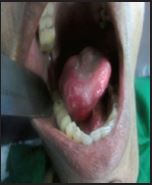

Before operation

Diseased tongue